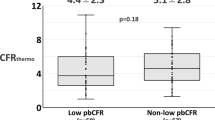

A total of 23 patients with CSX were enrolled, including 13 patients in the RIPC group, with 17 diseased vessels (nine vessels of eight patients in the UL subgroup and eight vessels of five patients in the LL subgroup), and 15 diseased vessels of 10 patients in the control group (six vessels of four patients in the UL subgroup and nine vessels of six patients in the LL subgroup). The results demonstrated that IMR decreased significantly in the experimental group after RIPC; no significant difference was observed in the control group (P > 0.05) (Fig. 3). Further data analysis demonstrated no significant difference in the decrease of IMR between the UL and LL subgroups of the RIPC group (P = 0.555) (Table 4).

As a coronary hemodynamic index, QFR can accurately reflect the changes in coronary blood flow. FAVOR series studies have fully confirmed the accuracy and feasibility of QFR in evaluating coronary blood flow and coronary function [10]. IMR and FFR are gold standards for evaluating coronary microcirculation dysfunction and coronary dysfunction, respectively. However, the current quantitative measurement method of IMR and FFR is complex, and cQFR and cQFR- fQFR are more economical and convenient than FFR and IMR in indicating coronary dysfunction. Lau [11] measured the changes in IMR and CFR after RIPC, confirming the effect of RIPC on coronary microcirculation and hemodynamics. This is consistent with the findings of the present study. Unlike the present study, this study used cQFR with cQFR-fQFR to measure coronary hemodynamics and microcirculatory function, which are more simply and convinient. The cQFR-fQFR in this study showed the same statistical results as the IMR, this may indicate that cQFR-fQFR has similar validity to the IMR in assessing microcirculatory function.To our knowledge, this is the first study to confirm that RIPC can improve coronary function and increase coronary flow by measuring QFR and IMR.

There has been conflicting evidence regarding the effect of RIPC on coronary microcirculation. In the LIPSIA-Conditioning trial, four cycles of 30 s reperfusion or post-conditioning failed to improve the myocardial rescue and microvascular occlusion, post-conditioning combined with distal ischemic preconditioning for three cycles of 5-minute upper arm ischemia or 5-minute reperfusion improved myocardial rescue but did not significantly reduce microvascular occlusion [12]. Lau’s study also found that 3 cycles of 5-minute ischemia with 5-minute reperfusion improved coronary blood flow and microcirculation [11].Traverse et al. reported that ischemic postconditioning did not reduce myocardial infarction area; however, reduced microvascular obstruction accelerated the recovery of left ventricular function in patients with STEMI [13]. Therefore different findings may be due to different RIPC protocols.In our study, IMR and c-fQFR were used to verify that RIPC can improve coronary microcirculation in CSX patients for the short term, and the change of cQFR suggested that short-term application of RIPC can increase coronary blood flow.